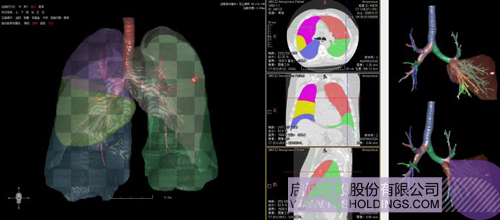

醫療影像智能診斷技術醫療影像智能分析是指運用人工智能技術、計算機視覺技術以及計算幾何技術對醫療影像進行自動分析,幫助醫生定位病癥、分析、跟蹤病情,并通過量化數據輔助醫生做出診斷,目前其旗艦產品“數字肺”已經覆蓋多種肺部疾病的早期檢測、診斷、跟蹤、術前規劃等完整的醫療流程。在臨床實踐中,超過80%的醫療數據來自醫療影像,這些影像數據通常需要專業醫生進行解讀,工作的重復性高、效率偏低。如果能夠運用智能影像分析技術,同時結合臨床表現以及既往病例進行全面分析,那么就可以大幅度提升影像診斷效率和準確性,讓專業醫生的寶貴時間集中在復雜病情的診斷和治療等環節。

數字肺——肺結節手術規劃系統

(1)計算/微分幾何用于分析、量化、可視化影像中所變現的各類組織以及病變等形態特征,機器學習主要對影像以及相關病變進行分類等定性分析并輔助一些定量分析,是服務臨床的一個重要模塊或者環節但不是唯一的環節。上述兩者在影像分析中互為補充、彼此增強,構建了神州德信智能影像分析的技術基礎。

完整的三維影像智能分析技術;

完整的三維可視化以及相關建模、幾何分析技術;